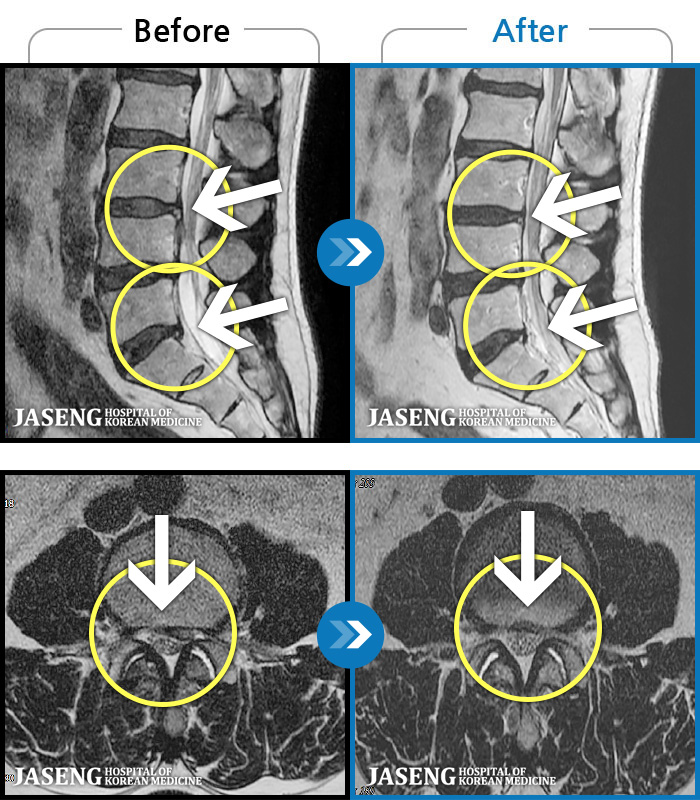

MRI ġ

1,237 MRI ũ ʸ Ȯϼ.